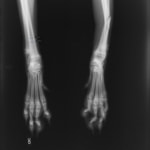

中足骨骨折 : 症例1 | 症例2

症例3:キルシュナーワイヤーのピンニングによる整復

ペルシャ猫 11ヶ月齢 雄

他院にて左大腿骨遠位の成長板骨折(salter-harrisⅠ型)が認められており、治療相談を目的として来院。当院にて、キルシュナーワイヤーを用いたピンニングにより骨折部位の整復を行いました。術後の経過は良好で、現在も経過観察中です。

術前レントゲン

術後レントゲン